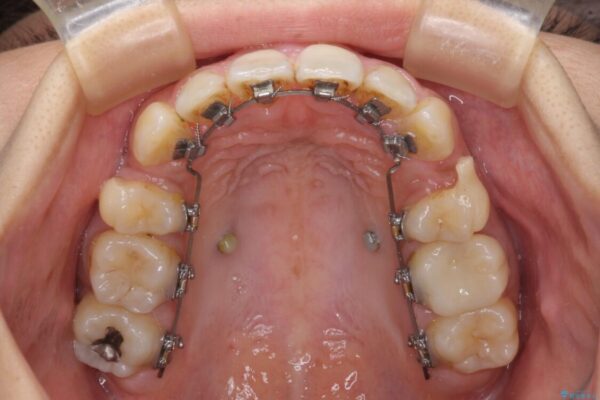

治療途中

• デコボコと口元の突出感 ハーフリンガルでの抜歯矯正 治療途中画像